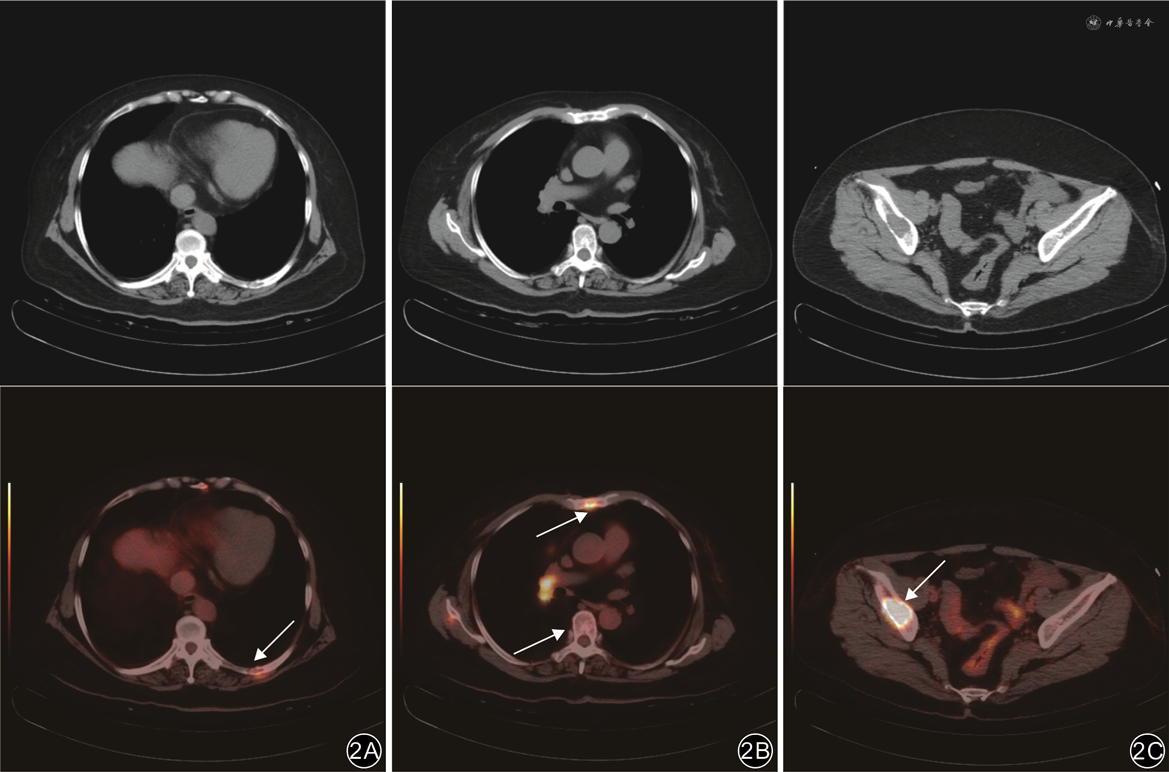

肺癌骨转移和前列腺癌骨转移病灶以高代谢为主,SUVmax较高,分别为5.70~29.10(15.51±5.60)和4.30~15.10(9.41±3.47)。在42例肺癌骨转移病例中,有41例(97.6%)显示SUVmax≥6.0;而在30例前列腺癌骨转移病例中,有24例(80.0%)显示SUVmax≥6.0。MM病灶以弥漫性轻中度代谢为主,SUVmax较低,为0.80~12.00(5.39±2.84)。在36例MM病灶中,有12例(33.3%)显示SUVmax≥6.0。3组间SUVmax比较差异有统计学意义(F=54.66,P<0.001),组间两两比较差异均有统计学意义(P值均<0.05)。

注:上排为CT图像;下排为对应位置的正电子发射体层摄影(PET)/CT融合图像